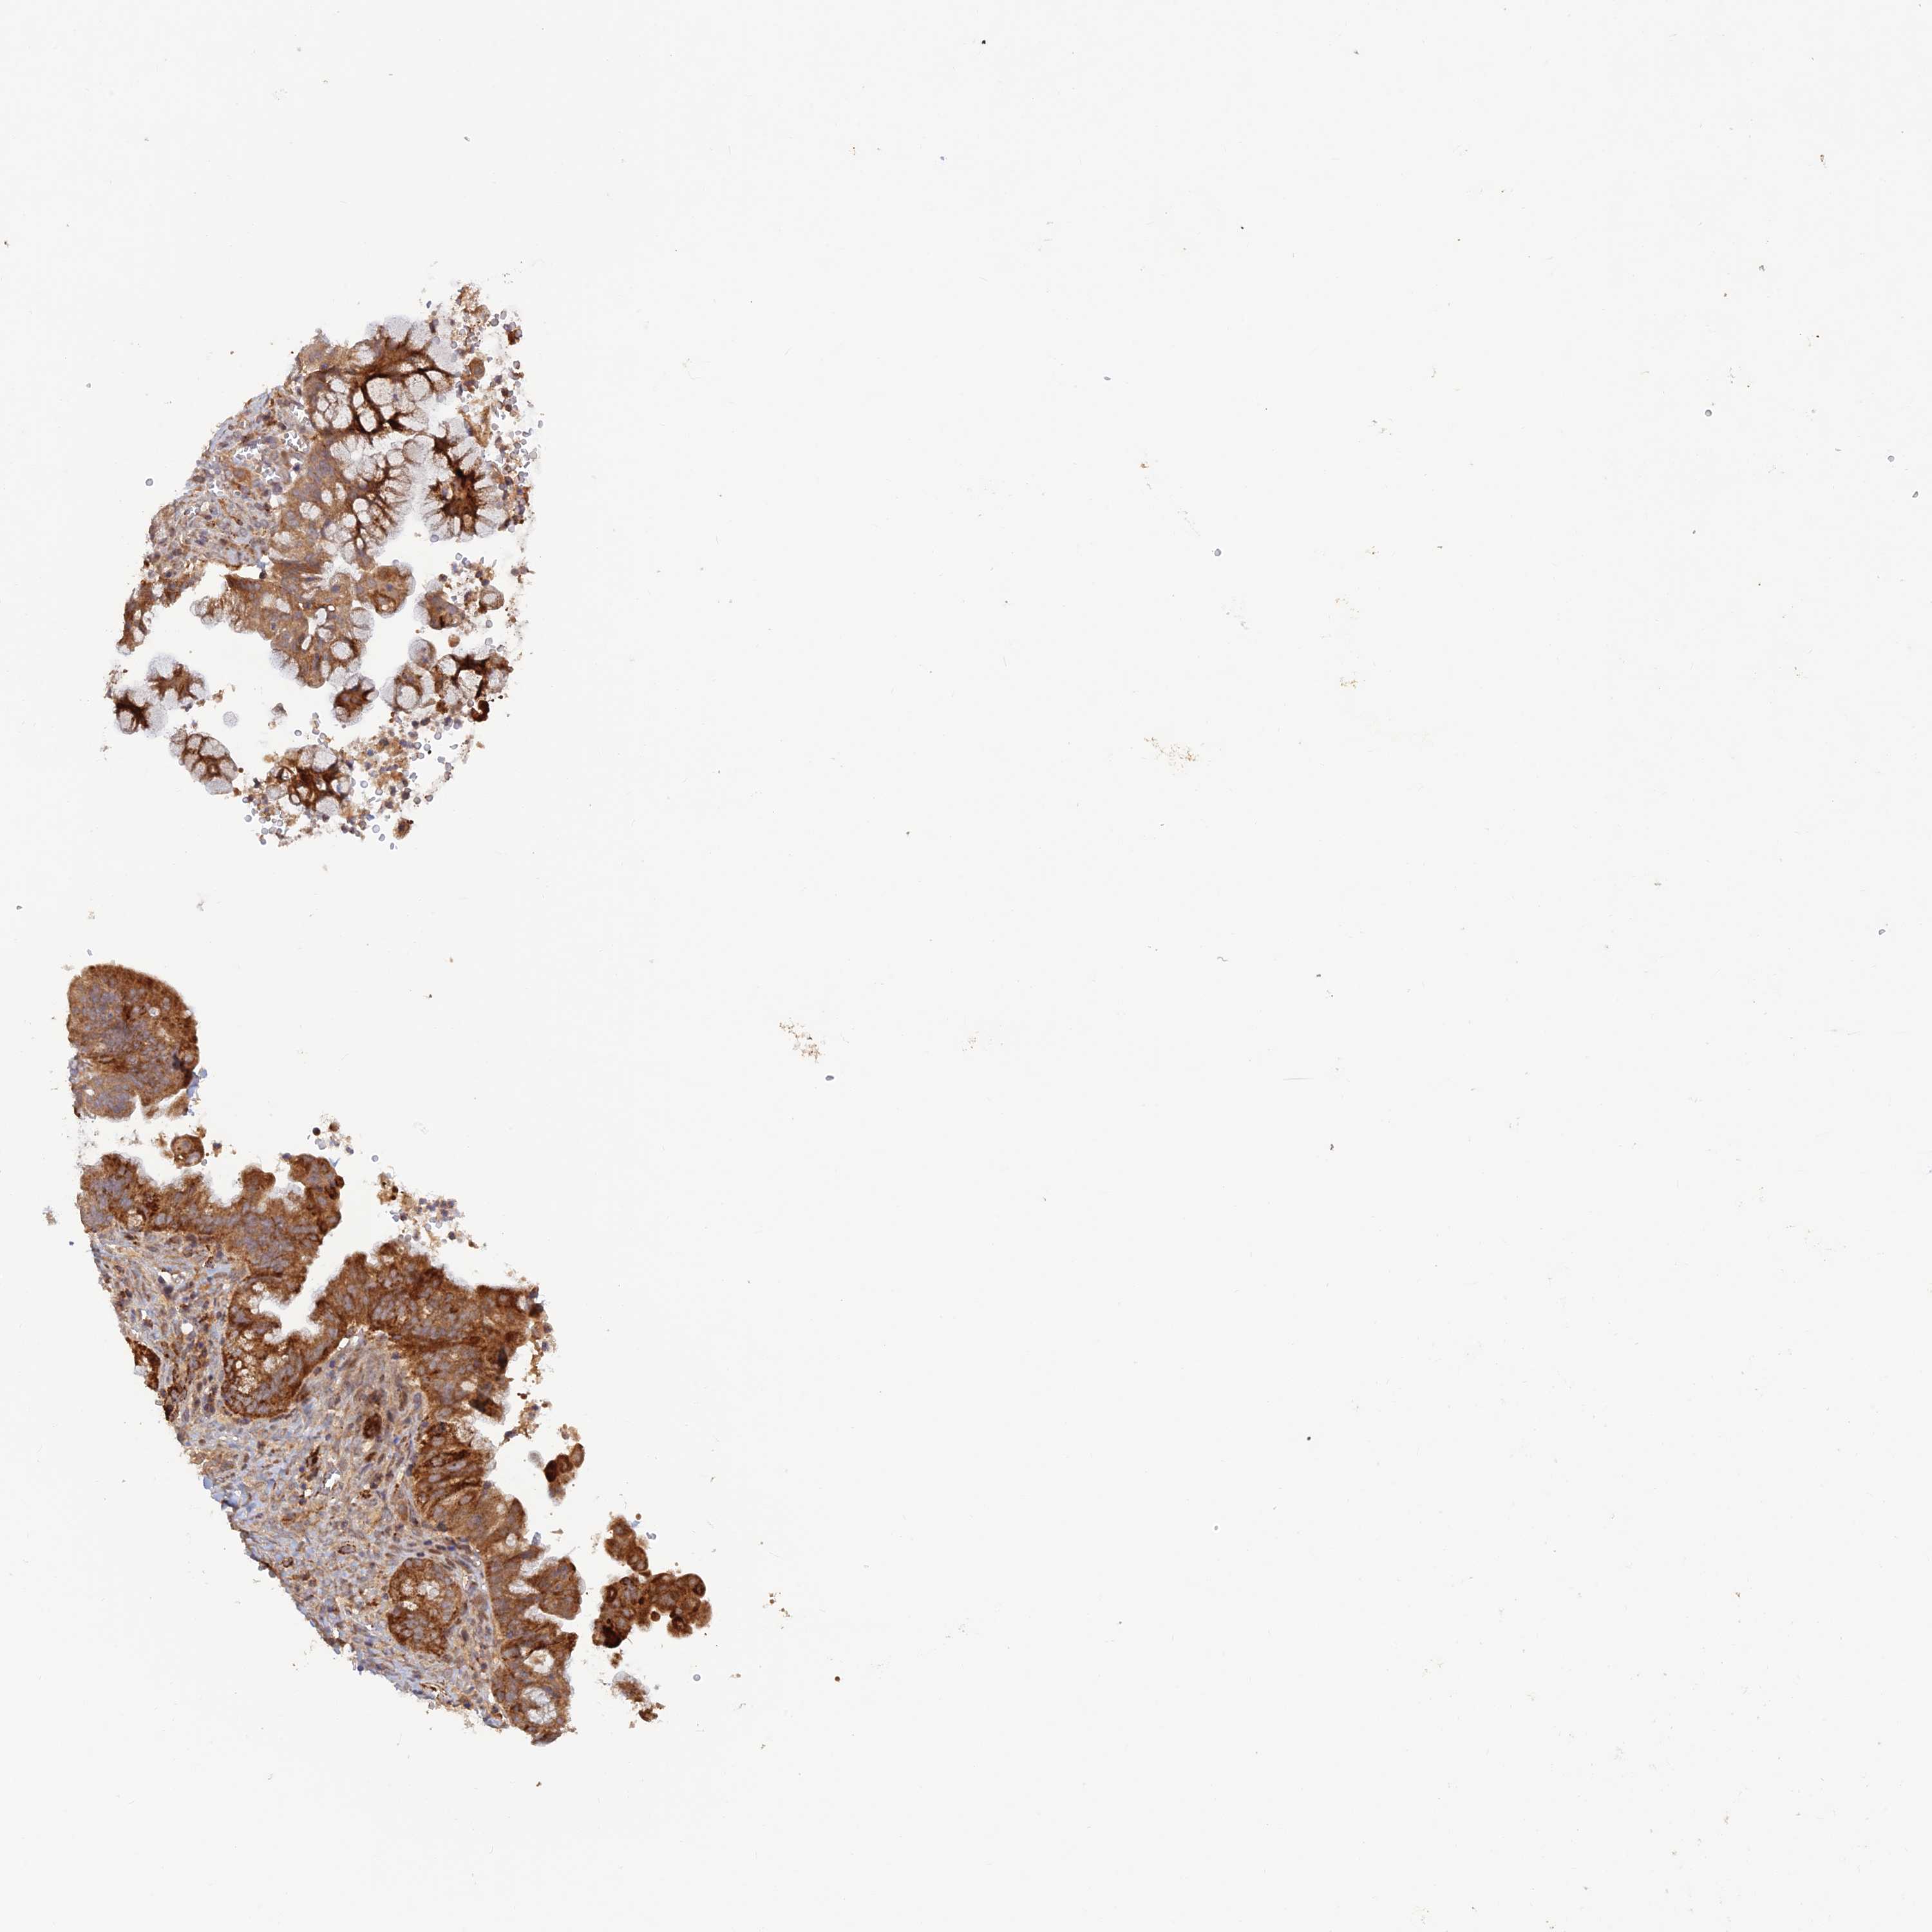

OVARIAN CANCER - Protein expressioni

A mouse-over function shows sample information and annotation data. Click on an image to view it in a full screen mode. Samples can be filtered based on level of antibody staining by selecting one or several of the following categories: high, medium, low and not detected. The assay and annotation is described here.

Note that samples used for immunohistochemistry by the Human Protein Atlas do not correspond to samples in the TCGA dataset.

Antibody stainingi

Antibody staining in the annotated cell types in the current human tissue is reported as not detected, low, medium, or high, based on conventional immunohistochemistry profiling in selected tissues. This score is based on the combination of the staining intensity and fraction of stained cells.

Each image is clickable and will lead to virtual microscopy that enables deeper exploration of all samples and also displays staining intensity scores, fraction scores and subcellular localization as well as patient and tissue information for each sample.

Antibody HPA043551

Staining

High

Medium

Low

Not detected

Intensity

Strong

Moderate

Weak

Negative

Quantity

>75%

75%-25%

<25%

None

Location

Nuclear

Cytoplasmic/membranous

Cytoplasmic/membranous,nuclear

Cystadenocarcinoma, serous, NOS

Carcinoma, NOS

Cystadenocarcinoma, mucinous, NOS

Carcinoma, endometroid